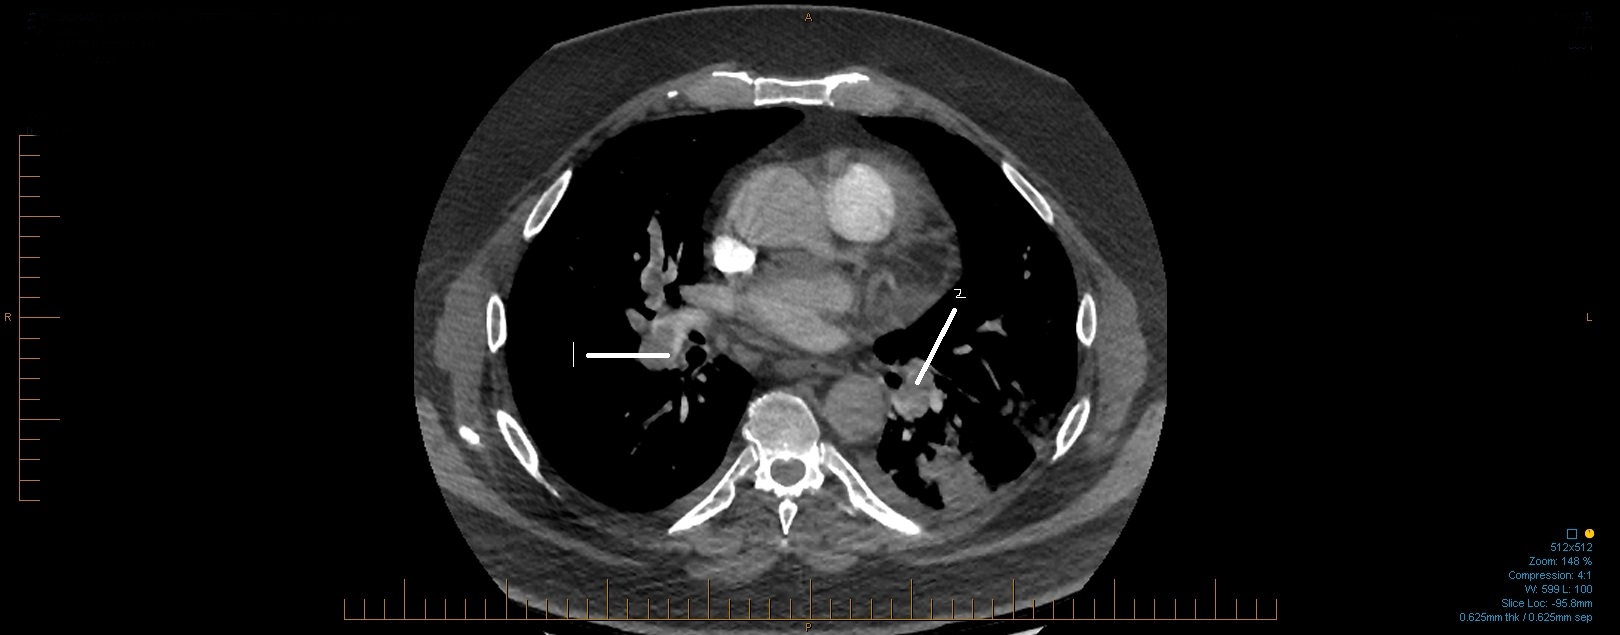

Pulmonary Embolism

Suboptimal opacification of the pulmonary arteries.With this in mind, there are filling defects extending into the right

and left main pulmonary arteries in keeping with extensive central pulmonary emboli.